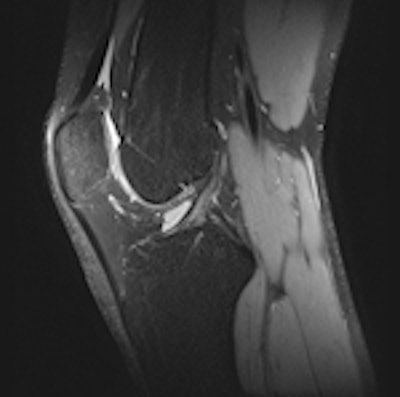

3D SPACE sequence performed at 3 tesla in a 21-year-old man. All scans are 1-mm multiplanar reformatted images in the sagittal (left), axial (middle), and coronal (right) plane. The patient had no abnormalities at arthroscopy. This case illustrates that all relevant structures (menisci, ligaments, and cartilage) can be visualized well using this sequence with good contrast-to-noise ratio between cartilage/meniscus and synovial fluid. All images courtesy of Dr. Pieter Van Dyck.Because uncertainty remains as to whether a single 3D TSE acquisition can replace the multiple conventional 2D acquisitions, studies are needed to determine the diagnostic usefulness of 3D TSE in future knee MR protocols at 3 tesla, Van Dyck and colleagues wrote in an article published online on 26 October by Insights into Imaging. The purpose of their retrospective study was to assess the diagnostic performance of the 3D TSE SPACE sequence, as compared with routine 2D TSE sequences, for evaluating the menisci, anterior cruciate ligament (ACL), and cartilage of the knee joint in symptomatic patients at 3 tesla.

The 3D protocol consisted of a single 3D TSE acquisition in the sagittal plane with the SPACE sequence. The SPACE isotropic source data were postprocessed on a workstation (Leonardo, Siemens Healthcare) to create sagittal, coronal, and axial multiplanar reformatted (MPR) images with 1-mm slice thickness. Readers were free to use volumetric data to create MPRs in any orientation and slice thickness, they stated.